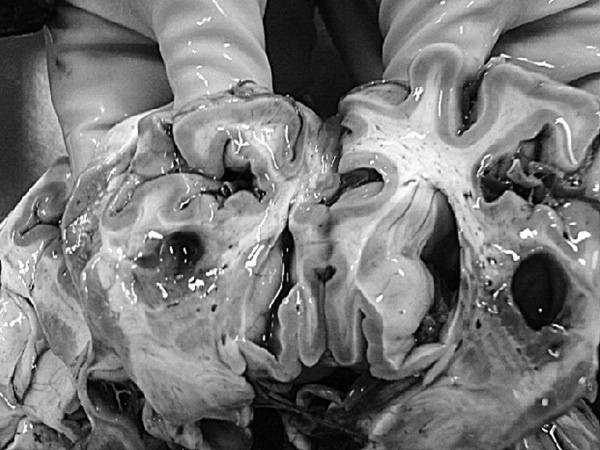

Доброкачественная гиперплазия предстательной железы

Рис. 1. Результаты аутопсии больного 68 лет

В рамках академической книги, естественно, следует выдерживать определенный стиль изложения, хотя каждому понятно, что на протяжении 12 лет практически помощи пациенту не было. Но тем не менее давайте вместе проанализируем факты, так как они изложены в амбулаторной карте. Итак, начнем с диагноза ИБС, после которого вместо определения клинической ее формы (постинфарктный кардиосклероз, хроническая аневризма и т. д.) доктор пишет морфологический диагноз: атеросклероз коронарных сосудов. В клинике этот диагноз может быть выставлен только при условии имеющейся коронарографии. Далее за 12 лет нет информации об ЭКГ, нарушениях ритма и пр. Поэтому и форму ИБС установить затруднительно, уже не говоря об отсутствии за столько времени ЭХОКГ. Но тем не менее диагноз был выставлен, были все показания для назначения обоснованной терапии. Ни обоснований, ни самой терапии в амбулаторной карте нет. В 2003 году пациент переносит ОНМК, после чего ему назначают курсами винпоцетин и пирацетам. Трудно комментировать эти назначения, поскольку нет не только доказательной базы эффективности указанных препаратов, но и обоснованных рекомендаций по их применению у больных после перенесенного инсульта. Далее с 2004 по 2007 год единичные осмотры терапевта и невролога по поводу жалоб на слабость в конечностях, головокружения и снижение памяти. Указания на иммобилизацию отсутствуют. Очевидно, что отсутствие наблюдения, медикаментозной и реабилитационной поддержки, а как вы узнаете и позже – отсутствие понимания значения маломобильности превратило существование пациента только в одно – самостоятельную борьбу за жизнь. Эта борьба была продолжена еще в течение 4 лет. Случайным осмотром отмечены трофические нарушения и отечность нижних конечностей, пролежни, снижение памяти и плохой сон. Интерпретации клинической дано не было, судить о причине отеков (сердечная недостаточность или местные кожные или сосудистые изменения) невозможно. Цифры АД не указаны (!). Но тем не менее был выставлен диагноз, в котором впервые прозвучала токсическая полиневропатия (что имелось в виду и какой токсикоз, осталось за кадром клинических мыслей врача), НК 1 и пролежни. Выписан феназепам по 0,5 мг на ночь (обещали придерживаться академизма, но выдержать сложно, цинизм в худшем его проявлении). Следующая запись через 2 месяца – констатация смерти. 68-летний пациент после смерти даже «не заслужил» посмертного эпикриза. По данным секции, у больного был очень высокий кардиоваскулярный риск (табл. 1), определяемый мультифокальным атеросклерозом, АГ и ХБП.